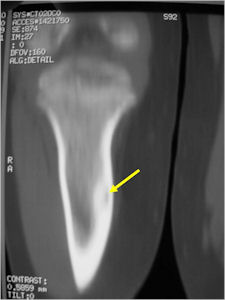

CT Scan:

- Well defined nidus with a smooth peripheral margin; +/- mineralization (CT more sensitive than XR and MRI for detecting mineralization); CT is better for detecting nidus in presence of exuberant sclerosis

- CT is more useful for detecting the nidus if there is extensive edema